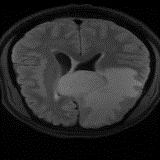

We obtain a subject-wise mean Dice score of 63.67% for the brain tumor segmentation. Utilizing a simple post-processing scheme of erosion and dilation with filter, we improve our mean Dice score to 68.01%. Figure 4 shows samples generated by our ASC-Net and Table 2 shows our before and after post-processing results. We attempted to apply f-AnoGANs [34] by following their online instructions and failed to generate good reconstructions as shown in Figure 5. The failure of AnoGANs in the reconstruction brings to light the issue with the regeneration based methods and the complexity and stability of GAN-based image reconstruction.

Brain Tumor Segmentation (BraTS 2019). In this task, we perform patient-wise two-fold cross-validation on the Brats-2019 training set. In each training fold, we use a 90/10 split after removing empty slices. The 2D slices from the 90% split without tumors are used to make our reference distribution ; while the 2D slices with tumors from the 90% split and all the slices from the 10% split are used for training our model. As a result, the sample size of for fold one and two amounts to 11,745 and 12,407 respectively, while the size of amounts to 11,364 and 10,786, respectively. We train this network using two cycles in the first stage and one cycle in the second stage.